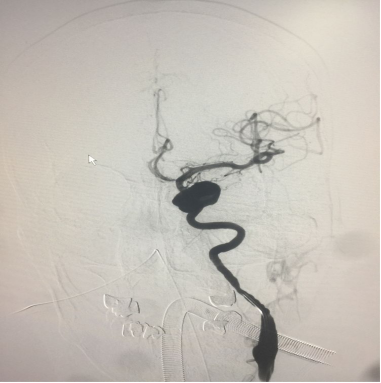

侧位片

动脉造影早期可见流入道及流出道

造影剂有滞留